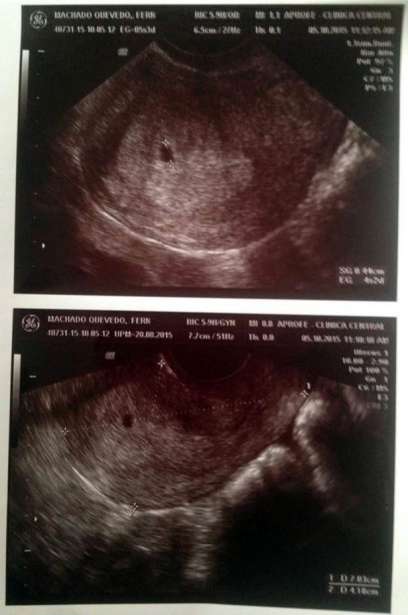

Scan revealing the expected Baby |